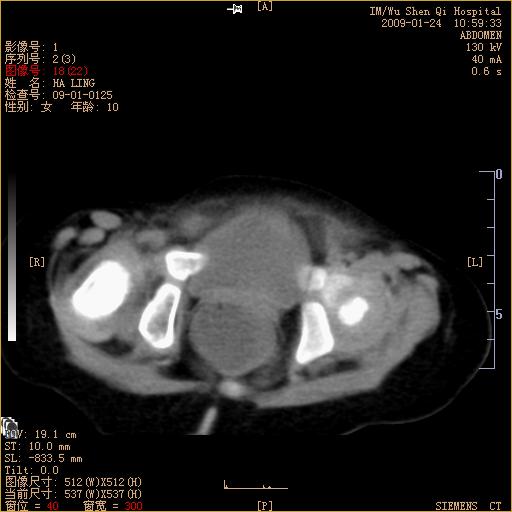

女 10岁 吐泻5天

低位肠梗阻.

肠管扩张!

肠管积气积液,还有液面,建议结合临床

扩张的肠管到直肠,麻痹性肠梗阻?

考虑巨结肠吗?

肠管积气、积液伴液平;建议结合临床(可能与腹泻有关)。

肠管积气、积液,直肠明显扩张(充满液体),不知检查前有否肛管注液,临床有吐泻5天病史,不应该考虑肠梗阻,不知什么临床为做ct检查?

先天性巨结肠应该首先考虑

肠管积气扩张,内有小液平,肠间脂肪间隙模糊,考虑不完全性肠梗阻可能性大.

考虑巨结肠。